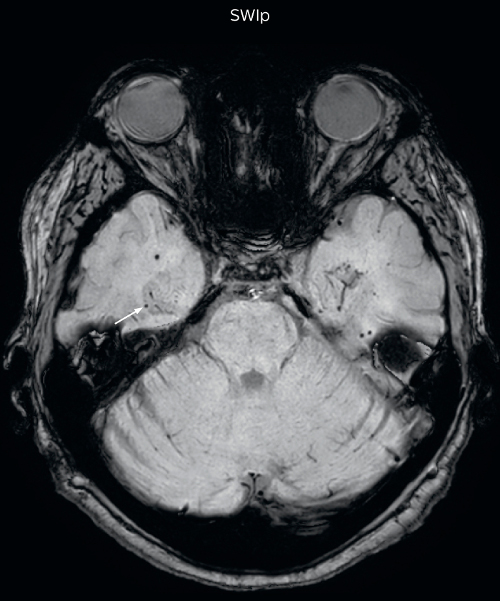

Hemosiderin foci in brain

Gradient echo imaging and SWIp are compared in a patient with radiation-induced foci of hemosiderin deposition. A greater number of small foci is seen on the SWIp image. Ingenia 3.0T

UVM case 1 FFE hemosiderin foci in brain1

UVM case 1 SWIp hemosiderin foci in brain1